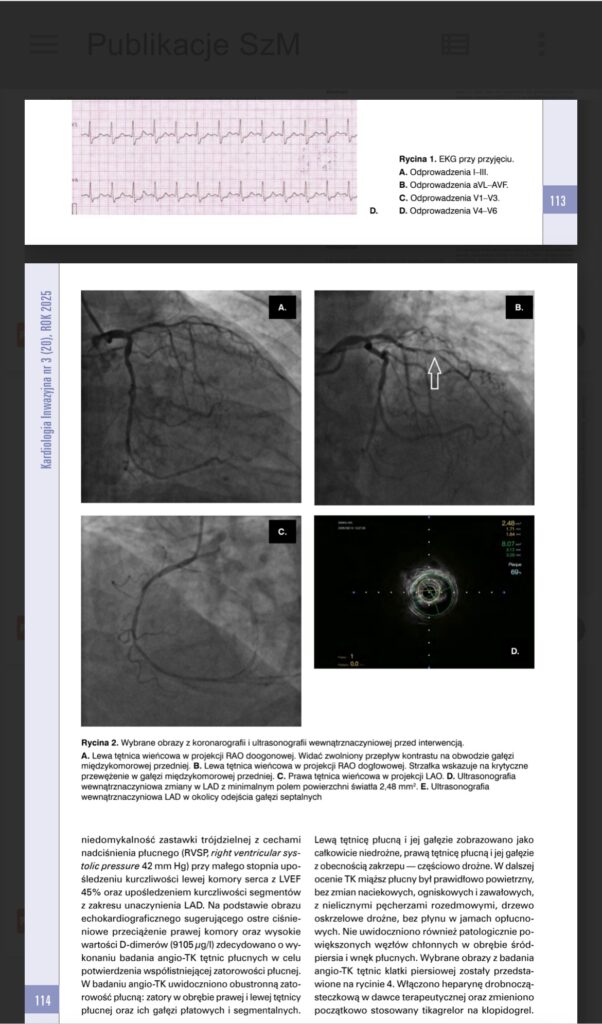

Pan Lech Rokita trafił do naszego szpitala z zawałem serca oraz jednoczesnym zatorem tętnicy płucnej – sytuacją niezwykle niebezpieczną, ponieważ zarówno serce, jak i płuca były zagrożone w tym samym czasie. Zator w płucach oznaczał zablokowany dopływ krwi, a tradycyjne metody leczenia niosły ze sobą wysokie ryzyko powikłań.

Przed rozpoczęciem leczenia zatorowości płucnej pacjent wymagał również angioplastyki krytycznie przewężonej głównej tętnicy wieńcowej, co stanowiło dodatkowe wyzwanie. Miesiąc po pierwszym etapie terapii pan Lech Rokita wrócił na drugi, planowy zabieg poszerzenia drugiego przewężonego naczynia, który zakończył się sukcesem. Dziś pacjent czuje się dobrze.